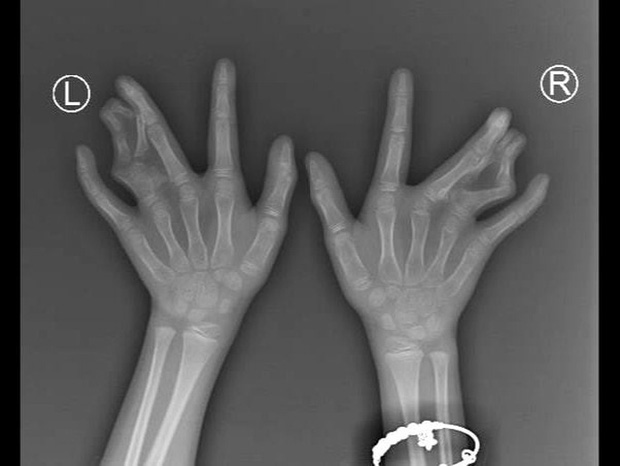

Bé N. từ khi sinh ra đã dính ngón 3, 4 cả 2 bàn tay và thừa ngón 4 cả 2 bàn tay. Gia đình bé bị di truyền tính trội bệnh này từ ông bà cố, cha, chú... Bé từng rong ruổi nhiều nơi, nhiều bệnh viện để điều trị, mổ phục hình nhưng đều thất bại.

Bàn tay "càng cua" di truyền qua nhiều thế hệ bé N

Tại Bệnh viện Nhi Đồng Thành phố, may mắn đã đến với bé N. Ê-kip chỉnh hình của BSCK1 Nguyễn Dương Phi đã tích cực hội chẩn liên tục với bác sĩ Terry Light, chuyên gia bàn tay Mỹ. Bé N. được đánh giá phân loại dị tật loại 3, dính phức tạp, không có kẽ ngón.